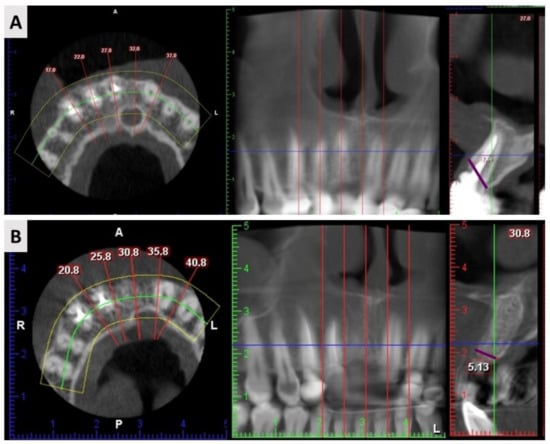

2.3. Cone Beam Computed Tomography (CBCT) Results

4.5. Radiological Assessment

| Width before Extraction | Width after Extraction | Net Change | |

|---|---|---|---|

| ADG 1 | 8.06 ± 1.34 mm | 7.18 ± 1.48 mm | −0.88 ± 0.76 |

| BX+AB 2 | 7.88 ± 1.08 mm | 6.64 ± 0.85 mm | −1.24 ± 0.99 |

| p-value * | 0.654 | 0.172 | 0.219 |